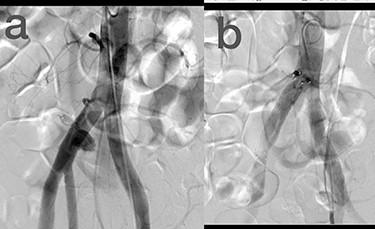

Sites of injury included 6 Posterior Tibialis arteries (27.2%) (Fig. 1), 2 deep femoral arteries (9.09%), 2 Superficial femoral arteries (9.09%) and 2 maxillary arteries (9.09%). We had only one injured artery (4.54%) in each of the following sites: internal pudendal a., Axillary a. (Fig. 2), Proneal a., Lumbar a., External carotid a., Anterior Tibialis a., common iliac a. (Fig. 3), temporal a., Thoracic aorta and Internal iliac artery (Fig. 4).

(a) Common iliac artery before intervention, (b) after stent-graft deployment.